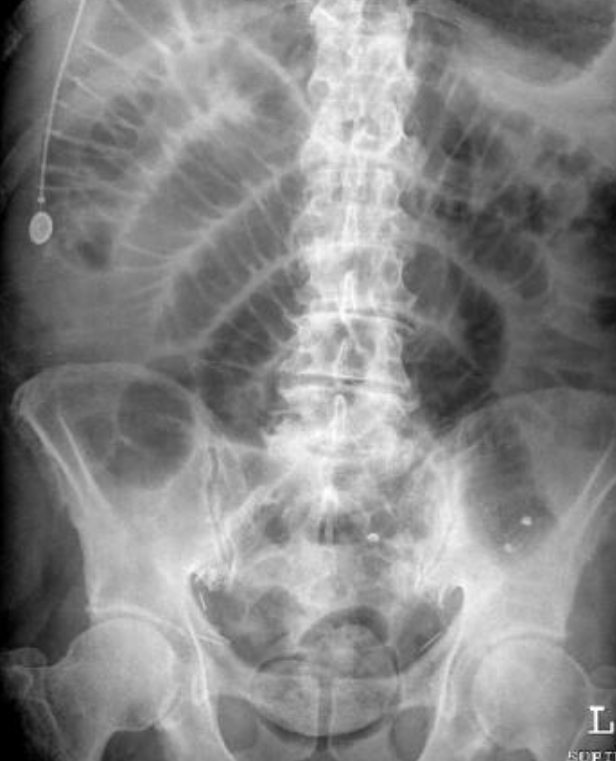

Large bowel obstruction

1- What is imaging technique? X-ray

2- what is your findings? Dilated + obstructive intestine

Mention 4 causes of this condition? Neoplasm, volvulus, polyp, hernia, adhesions, intussusception